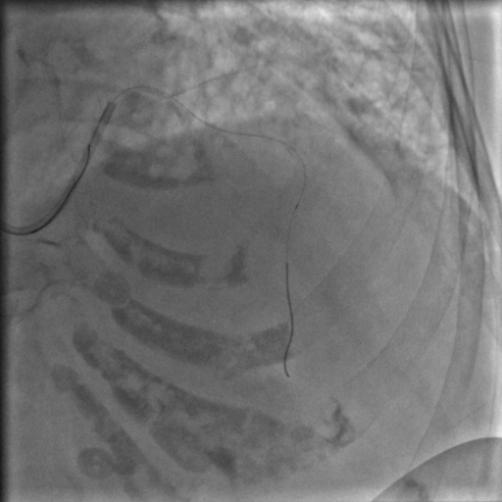

按照常规,更换指引导管,送入导丝,顺利通过闭塞病变到达前降支远端,很顺利,D-to-B时间70分钟,达标,曙光在前头。

图5

导丝过了之后常规造个影:

图6

没通,这个也很正常,急性冠脉闭塞导丝过了之后血栓还堵着是很经常的事,按常规打点欣维宁,考虑到她86岁,打入8ml欣维宁,造影: